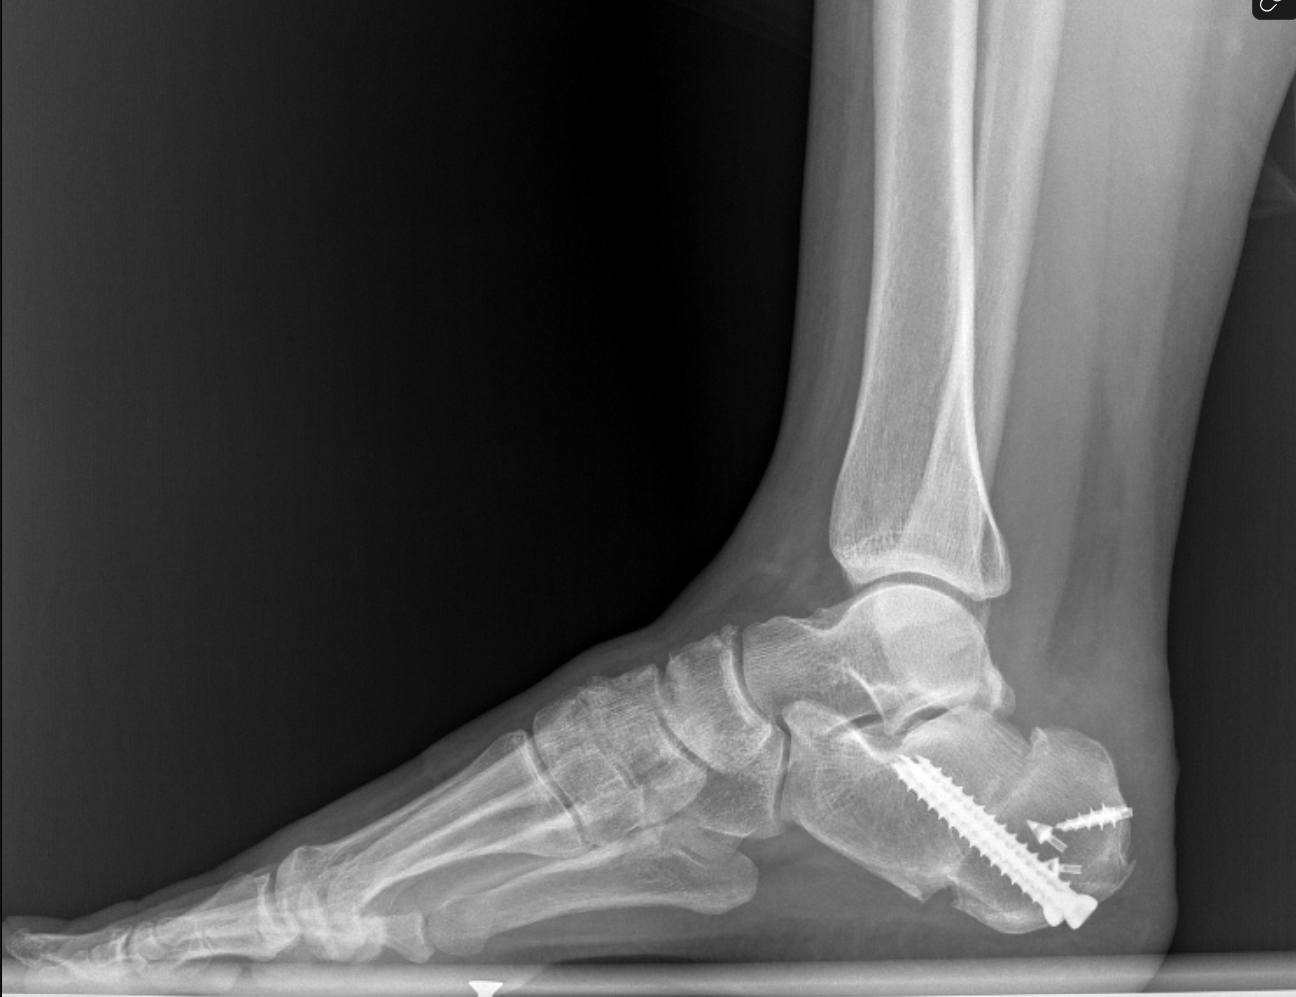

Postoperatif röntgen görüntüleri

- Zadek osteotomisi: Kalkaneusun arka kısmından kama çıkarılarak kemik çıkıntısı düzeltildi.

- Aşil tendonundaki dejeneratif kısım temizlendi.

- Çift sıra tamir (suture-bridge): Tendon sağlam bir şekilde topuk kemiğine yeniden tutturuldu.